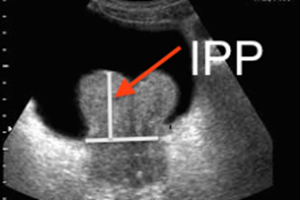

Il s’agit d’un troisième lobe pathologique à développement intra vésical. On le repère très bien par l’échographie sus pubienne où ce lobe médian apparait comme une hypertrophie en « pain de sucre » soulevant le plancher vésical.

Volumineux lobe médian prostatique avec Index de Protrusion Prostatique (IPP) de grade 3

On insiste actuellement sur l’indice de protrusion prostatique (IPP), correspondant à la mesure de cette protrusion dans la lumière vésicale.

Inférieure à 5 mm. cet IPP est de grade 1, modéré.

Au delà d’un centimètre, l’IPP est de grade 3, corrélé avec une gêne mictionelle clinique importante et une fréquence d’absence de reprise des mictions par les voies naturelles après rétention vésicale complète. C’est un élément venant à l’appui d’une indication chirurgicale.

Le grade 2 entre 5 et 10 mm. d’IPP est intermédiaire.

Le caractère dysectasiant de ces lobes médians prostatiques, c’est à dire l’importance de la gêne qu’ils entrainent pour la miction ainsi que leur retentissement péjoratif sur l’appareil urinaire et le risque de dégradation auquel ils l’exposent, est bien connu. Ils viennent s’appliquer sur le col vésical au moment de la miction faisant clapet sur lui.

Ils constituent une indication chirurgicale fréquente d’autant que le traitement médical à souvent peu d’effet sur leur évolution. Un retentissement très important peut exister même pour des lobes médians apparemment peu hypertrophiés, du fait de la position centrale au niveau de la filière cervico urétrale de ces lobes médians qui entrainent rapidement une compression mécanique et une obstruction du col vésical. Du fait du soulèvement du plancher vésical et de l’étirement du trigone, une portion de la vessie à l’innervation particulièrement riche, ils sont également à l’origine d’une symptomatologie irritative et inflammatoire souvent à l’origine de gênes très importantes pour les patients.